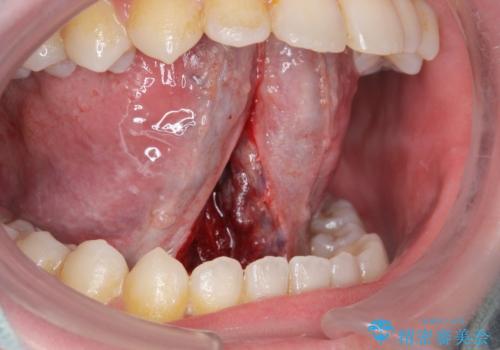

舌の動きの範囲が大きくなり、滑舌が良くなりました。

ラ行も言いやすくなったそうです。

舌小帯の形成術は当日に行うことができます。

- 外科手術のため、術後に出血、痛みや腫れ、違和感を伴います